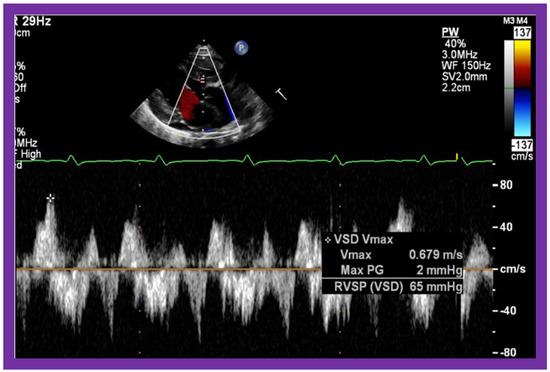

Then, the ventricular septum is evaluated; the ventricular septum is intact in most Type Ia cases. In children with Type I (normally related great arteries), the VSD supplies the pulmonary blood flow (Figure 10) while in patients with Type II (transposition of the great arteries) the VSD allows the blood to flow into the systemic circuit (Figure 11; Figure 12). In Type I patients, the VSD is demonstrated by 2D (Figure 10A), and the left to right shunt across it by color (Figure 10B), pulsed and CW (Figure 10C) Doppler signals. The interrogation of the RV outflow tract and PA region should be performed; recording the peak Doppler flow velocity across the RV outflow tract and the pulmonary valve is helpful in identifying obstruction across these sites. The Doppler data from the VSD and RV outflow tract are also helpful in the estimating of PA pressures. In Type I babies, the 2D size of the VSD and the peak Doppler flow velocity across it are useful in quantifying the size of the VSD (Figure 10). The higher the VSD Doppler flow velocity, the smaller the defect. However, in patients with pulmonary hypertension or severe infundibular or valvar pulmonary stenosis, the VSD Doppler velocities are not reflective of the size of the VSD. Barring these exceptions, RV and PA systolic pressure may be estimated using a modified Bernoulli equation (RV/PA systolic pressure = systolic blood pressure – 4V2).

Figure 10. Selected video frames from parasternal long axis views of a patient with tricuspid atresia with normally related great arteries demonstrating an enlarged left atrium (LA) and left ventricle (LV), a small right ventricle (RV) and a moderate sized defect (VSD) (thick arrow) on 2D (A) and color flow (B) imaging. The turbulent flow (B), with a Doppler flow velocity of 2.91 m/s by continuous wave Doppler (C) across the VSD, suggests some restriction of the VSD. Ao, Aorta; PA, pulmonary artery. Reproduced from Reference [29].

Applsci 11 09472 g010